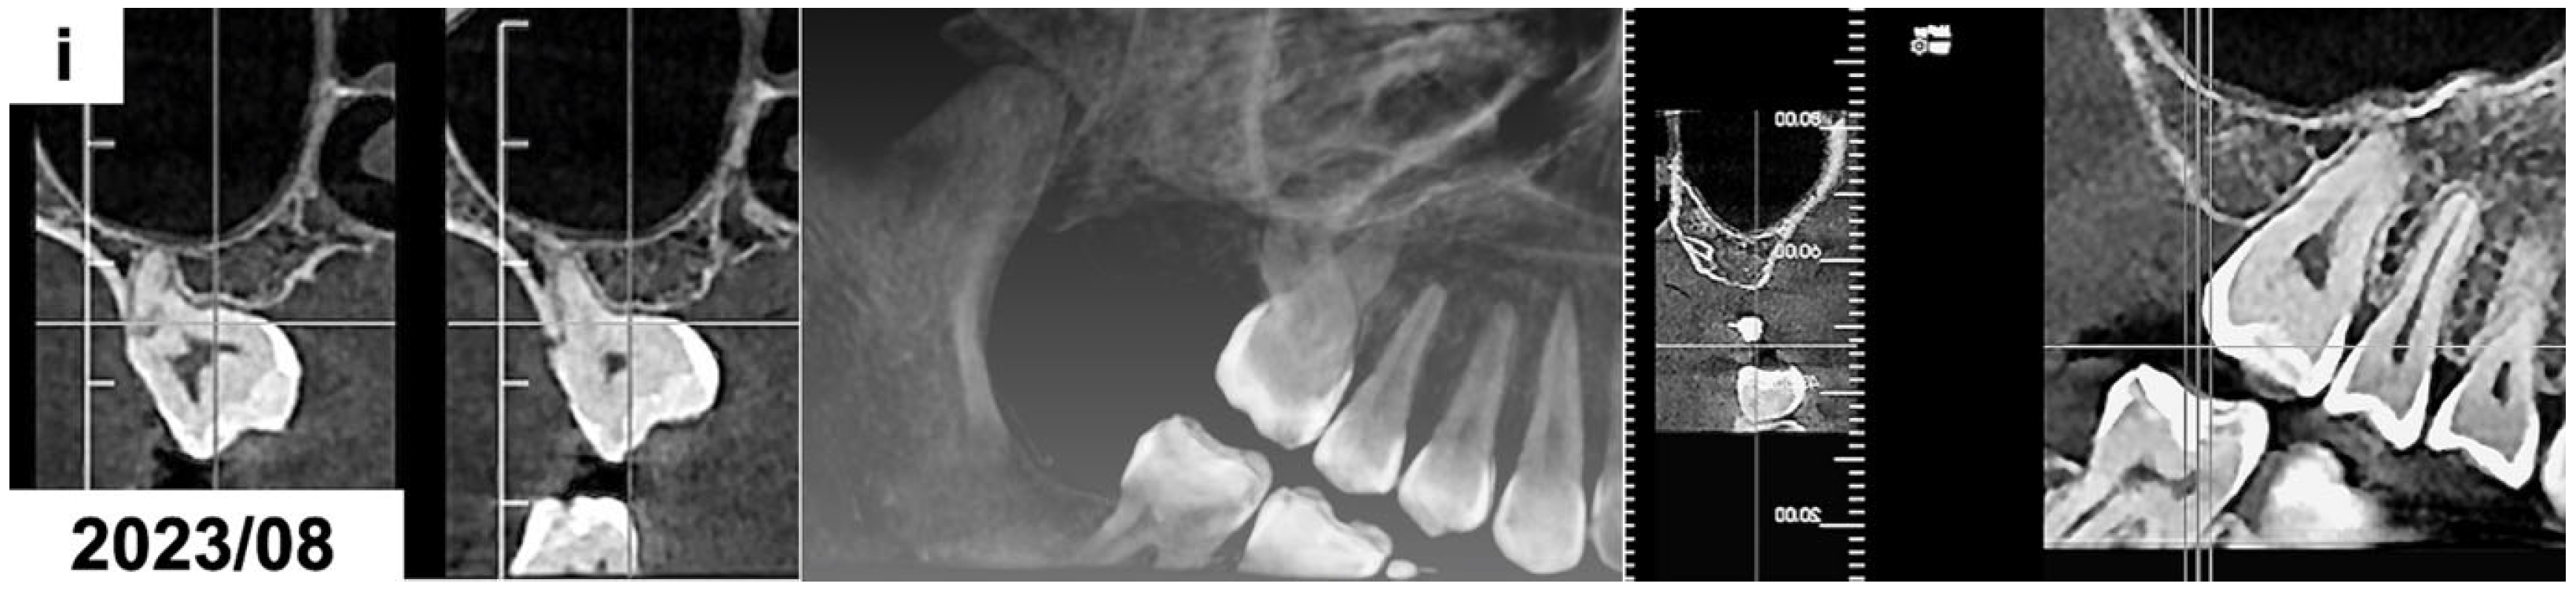

(a) CBCT examination scans before the treatment presenting the odontogenic tumor in the right maxillary molar region. The patient was 15 years and 10 months old. (b) CBCT examination scans after the surgical removal of the tumor presenting the malposition of the impacted permanent upper right first molar. The patient was 16 years and 4 months old. (c) Panoramic radiograph after the treatment, presenting the impacted maxillary. The patient was 16 years and 7 months old. (d,e) Intraoral photographs 10 months after the surgical treatment before the use of orthodontic traction with a segmented fixed appliance. The patient was 16 years and 7 months old. (f) Intraoral photographs 1 year and 4 months after the orthodontic traction of the permanent upper right first molar. The patient was 17 years and 10 months old. (g) Panoramic radiograph 6 years after the surgical and orthodontic treatment. The patient was 24 years and 1 month old. (h) Intraoral photographs 6 years after the surgical and orthodontic treatment showing the erupted permanent upper right first molar and its position in the dental arch. The patient was 24 years and 1 month old. (i) CBCT examination scans 6 years after the surgical and orthodontic treatment presenting the erupted permanent upper right first molar and the absence of the alveolar bone at the site of the tumor removal. The patient was 24 years and 1 month old.

The result of a histopathological examination with H&E staining revealed the presence of mature tubular dentin with the spaces containing small amounts of enamel matrix or immature enamel—the mature enamel was removed during the decalcification process. Therefore, based on the clinical, radiological, and histological examinations, the diagnosis of a complex odontoma was confirmed. The impacted maxillary molar was left for observation, but no signs of its spontaneous eruption were seen for 10 months (Figure 2c–e). Therefore, an orthodontic traction with a segmented fixed appliance was planned (0.022 slot, American Orthodontics, Mini Master series). Orthodontic brackets were bonded on the maxillary canine and premolars on the right side. The teeth were aligned after 3 months, and a stainless-steel rectangular wire (0.017 × 0.022 SS) was placed. The impacted tooth was attached to the appliance using an elastomeric Powerchain attached to the metal ligature. The Powerchain was scheduled for changing every 5–6 weeks. The impacted molar was successfully extruded in the oral cavity after 1 year and 4 months (Figure 2f); however, the patient missed some appointments. The patient refused to continue her orthodontic treatment to correct the posterior crossbite after the extrusion of the impacted molar. The orthodontic appliance was debonded, and no retention was used. The patient missed scheduled follow-up appointments and presented for re-evaluation 5 years after finishing the orthodontic traction. The maxillary right first molar was present in the oral cavity without any signs of pathology (Figure 2g,h). The cone-beam computed tomography revealed the absence of the alveolar bone at the site of the tumor removal. It was recommended to perform bone augmentation procedures before further implantation (Figure 2i).